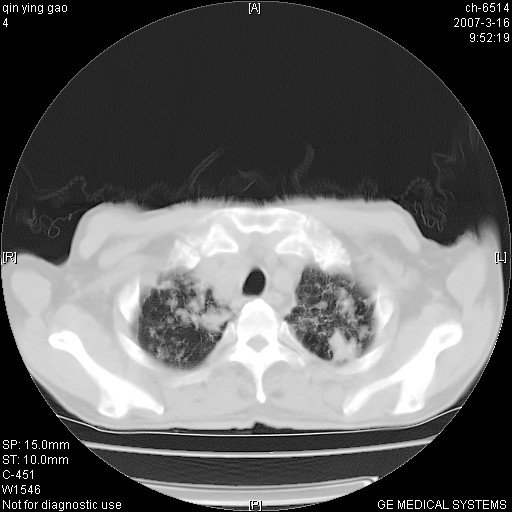

男,64岁.乏力2个月,畏寒、发热1月余。体重下降。血沉加快,白细胞不高。

两中上肺见有广泛新老不一的结节灶,并伴有纤维索条影,血沉加快,白细胞不高,首先考虑结核。

双肺以中上肺野为著斑片状.结节壮密度增高影 左上肺前段可见小类圆钙化灶 纵隔淋巴结无明显肿大

双肺可见大小不等结节状密度增高影,密度不均,分布不均(双肺上叶为著),亚急性血行播散性肺结核.

(本例特征:以大小不等结节为主,主要分布在双上肺,并部分病灶融合成较大结节,期间搀杂诸多细小结节。从病灶特点与分布形式分析,更趋向于感染。)

男,64岁.乏力2个月,畏寒、发热1月余。体重下降。血沉加快,白细胞不高。 双肺可见大小不等结节状密度增高影,密度不均,分布不均(双肺上叶为著),亚急性血行播散性肺结核.

中上肺野密布棉团状影,以胸膜下区为界,边缘模糊,可能是小叶或腺泡渗出及实变。全肺野弥漫分布网线样影及细小粟粒样影,可能是细支气管炎及间质内炎症。综合分析应首先考虑气道播散性感染,而肺内多处斑点性钙化,强烈提示陈旧结核复发并支气管播散。建议详细讯问病史

病变以两肺上野为著,部分病灶有钙化,纵隔窗显示病灶有新老不一,这个首先和结核脱不了干系,还有部分病灶有融洽的倾向,肿瘤也不能完全排出